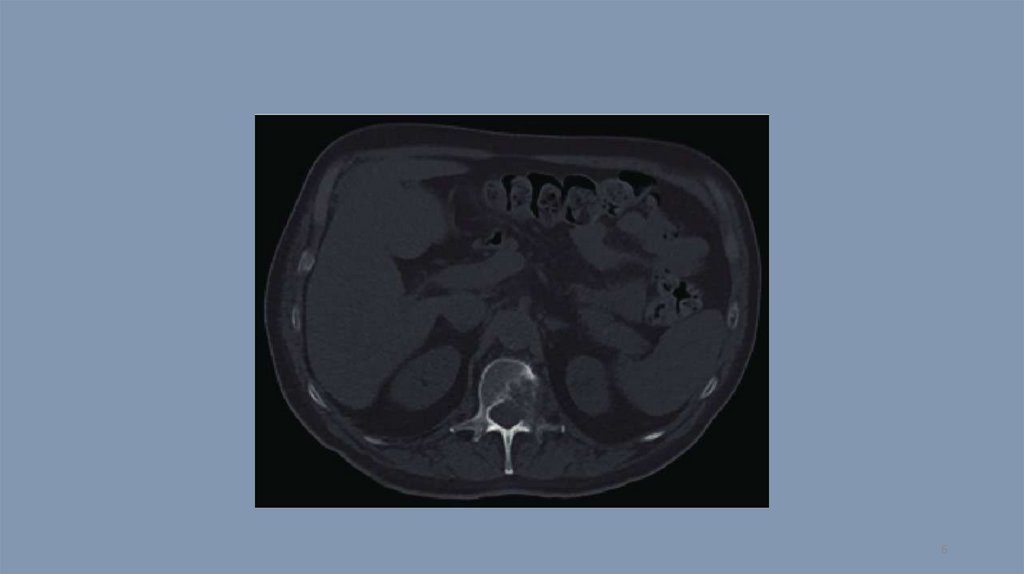

Компьютерная томография. Тест 14